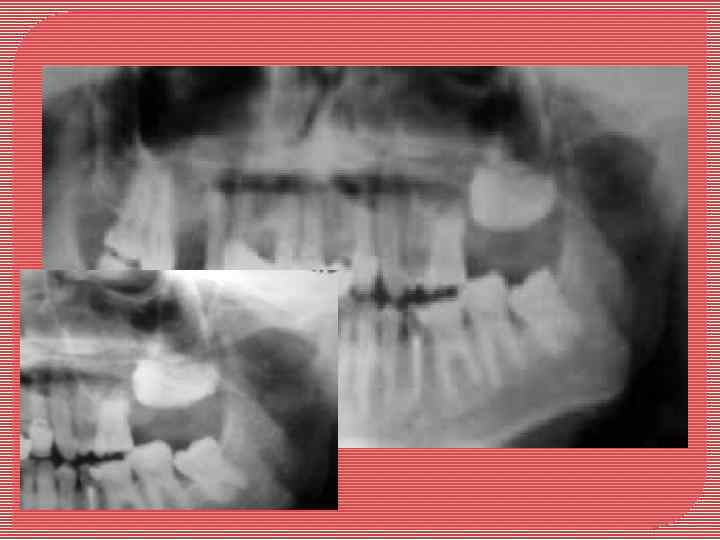

Амелобластома

нижней челюсти. Деструкция тела и ветви (рентгенограмма).

Амелобластома нижней челюсти (многокамерный вариант) Деструкция тела и ветви Между участками деструкции кости (полостями) четко выявляются перегородки (рентгенограмма).